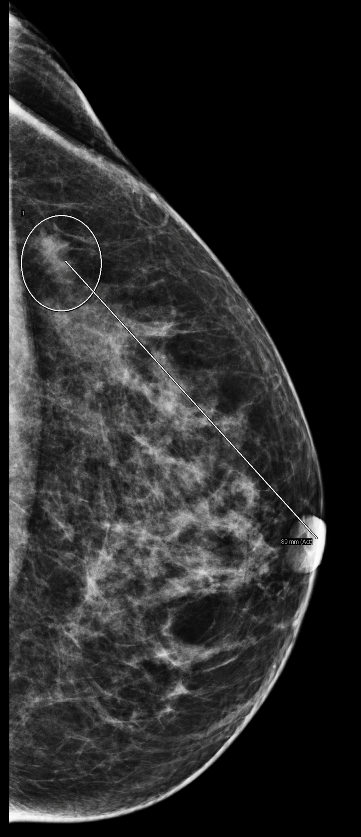

An asymmetry has been found in the left breast, at the far posterior upper outer quadrant. The tomosynthesis highlighted a spiculated mass at the location of the asymmetry, 9 cm from the nipple.

MammoScreen spots very well the spiculated mass in the tomosynthesis giving a score 9 of highest suspicion.